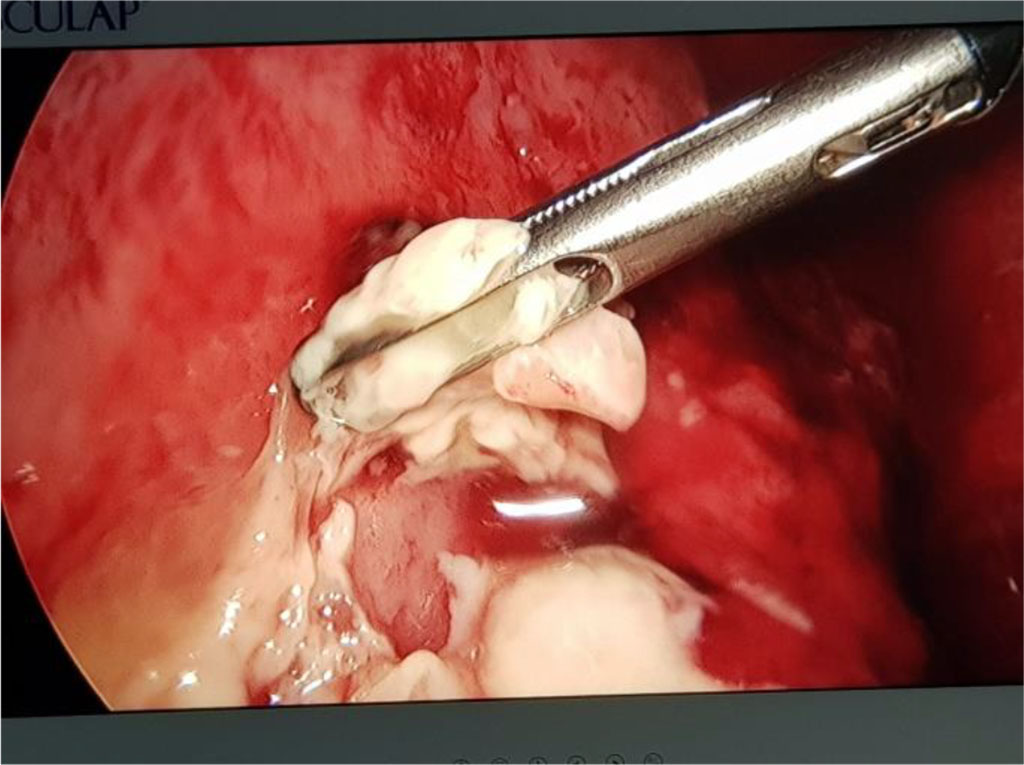

Seven days after the pleural drainage, another chest x-ray was performed. It revealed the maintaining of a non-homogeneous opacity in medium 2/3 of the right hemithorax (Fig. 8). Thus, a video-assisted thoracoscopy (VAT) pleuropulmonary decortication was done (Fig. 9). A subsequent chest x-ray revealed an ameliorated image (Fig. 10). Post-operatory evolution was slowly favorable despite the association between large spectrum antibiotic therapy and systemic antifungal therapy. The patient also needed supportive with rehydration perfusion, immunotherapy and blood transfusion for about one month.

Fig. 9. VAT for pleuropulmonary empyema